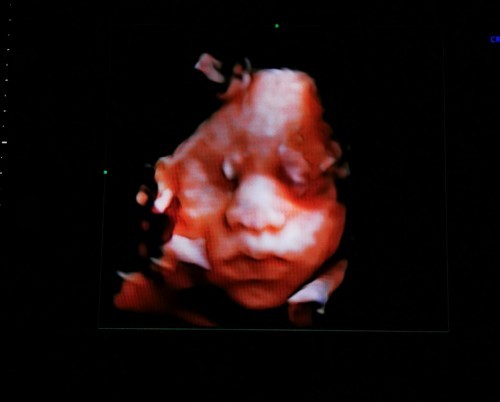

ภาพซาวด์4มิติ

ขอดูภาพซาวด์4มิติ ของแม่ๆท่านอื่นหน่อยคะ บ้านนี้ซาวด์ปัยน้องยิ้มเล่นไปด้วย ให้ทายว่าน้องเปนผญ.หรือผช.😊

หนุเป็นเด็กผุ้ชายคับแม่ๆ 32+5w